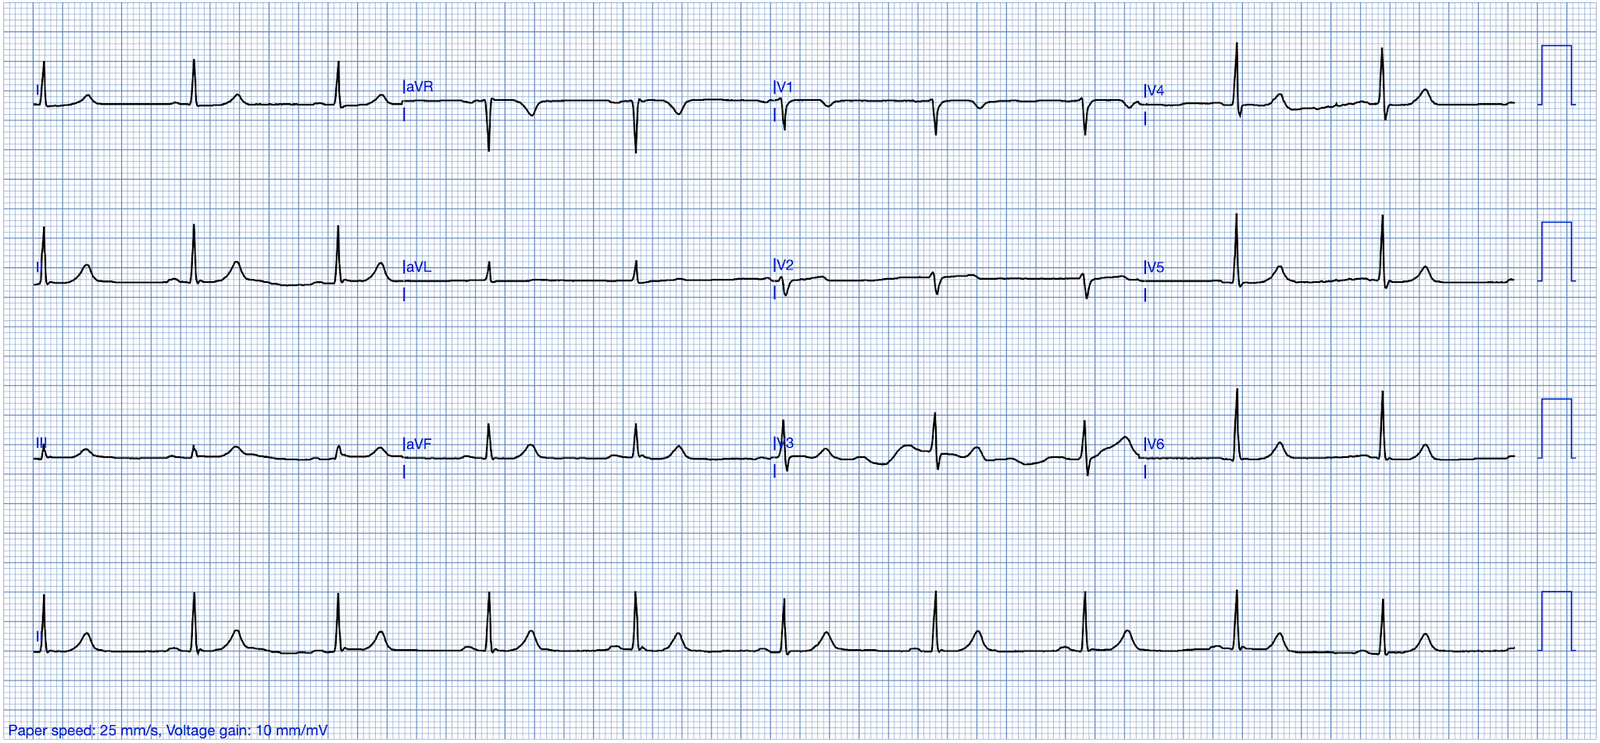

Here is her triage ECG:

— What do you think? —

Smith: This is classic for pulmonary embolism (PE). There are 2 key points to making this diagnosis on the ECG:

- 1) There is T-wave inversion which you might think is due to Wellens’ waves, but the patient has active symptoms, so it is not Wellens’ sydrome

- 2) The T-wave inversion in V1-V4 is accompanied by T-wave inversion in lead III. This is very specific for PE vs. ACS.

Also, and much less teachable: the T-waves just don’t look right for ACS.

We’ve reviewed the ECG clues to acute PE in those more than 20 links that Dr. Meyers’ lists above. I found today’s initial ECG interesting — in that most of the time, the ECG diagnosis of acute PE is highlighted by more than just a couple of the ECG Findings that I list below in Figure-2.

- For example, in today’s initial ECG (that I’ve reproduced and labeled in Figure-1) — there is no sinus tachycardia — and no right axis, RAA, incomplete or complete RBBB, tall R in lead V1, persistent precordial S waves, ST elevation in lead aVR or AFib.

That said — the following are present in today’s case:

- An S1Q3T3.

- Deep symmetric T wave inversion in the anterior chest leads (BLUE arrows in Figure-1) — that occurs in association with T wave inversion suggesting RV “strain” is present not only in the anterior chest leads, but also in inferior leads III and aVF.

PEARL (as per Drs. Meyers and Smith): When there is T wave inversion in the chest leads — IF there is T wave inversion in both lead V1 and lead III ==> Think acute PE (and not ACS! ).

- By itself — the S1Q3T3 sign seen in Figure-1 would not be specific for acute PE (ie, I have seen this sign in healthy individuals with no acute pulmonary pathology). However, in the presence of a suggestive history and the extensive T wave inversion seen in today’s case — the S1Q3T3 strongly supports the diagnosis of acute PE.

- T wave inversion as diffuse as is seen in Figure-1 — most often suggests a sizeable PE (which makes it all the more surprising that there is no tachycardia and a lack of more of those ECG findings that are listed in Figure-2).

- Finally — the Q in lead III — the ST coving with slight ST elevation + T wave inversion in leads III and aVF — and the ST segment straightening in lead aVL — might lead one to misinterpret today’s ECG as indicative of ACS. IF tempted to do so — it is worth rereading the above PEARL!